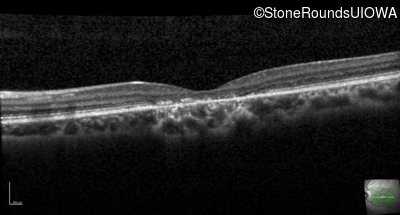

Optical Coherence Tomography - Right - 20/160

Exemplar / OCT Stack

OCT Stack